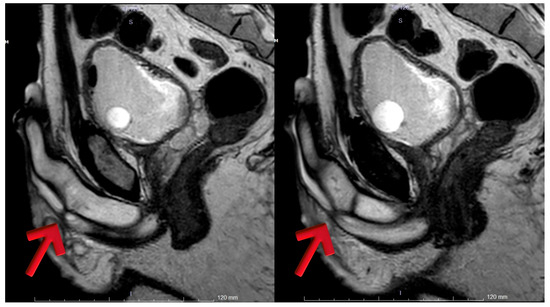

Background/Objectives: Conventional imaging modalities are often inadequate for evaluating the proximal extent of anterior obliterative urethral strictures. Magnetic Resonance Imaging (MRI), with its superior soft tissue resolution, provides detailed anatomical insights and significantly contributes to surgical planning in such cases. Methods: Four male patients aged 26–63 years with anterior obliterative urethral strictures were evaluated using MRI in addition to conventional imaging. All MRI scans were performed following a modified Joshi protocol. Clinical data, MRI findings, and surgical outcomes were retrospectively reviewed. Results: MRI successfully delineated stricture length, location, periurethral fibrosis, and proximal urethral status in all cases, correlating well with intraoperative findings. Case 1 showed a 2 cm proximal bulbar obliteration, excised with end-to-end anastomosis. Case 2 had a 2.5 cm distal bulbar stricture, managed similarly. Case 3 revealed multi-segmental strictures, treated with a combination of anastomosis, graft, and Kulkarni urethroplasty. Case 4 demonstrated a rare 9 cm distal penile obliteration with preserved proximal urethra, treated with anastomotic repair. MRI provided critical anatomical detail for surgical decision-making. Conclusions: MRI is a valuable imaging modality for the evaluation of anterior obliterative urethral strictures, particularly when the proximal extent of the stricture cannot be visualized with conventional imaging techniques. In our case series, MRI enabled precise delineation of the stricture length and surrounding anatomical structures, which was critical for selecting the most appropriate surgical approach. Full article

Figure 1